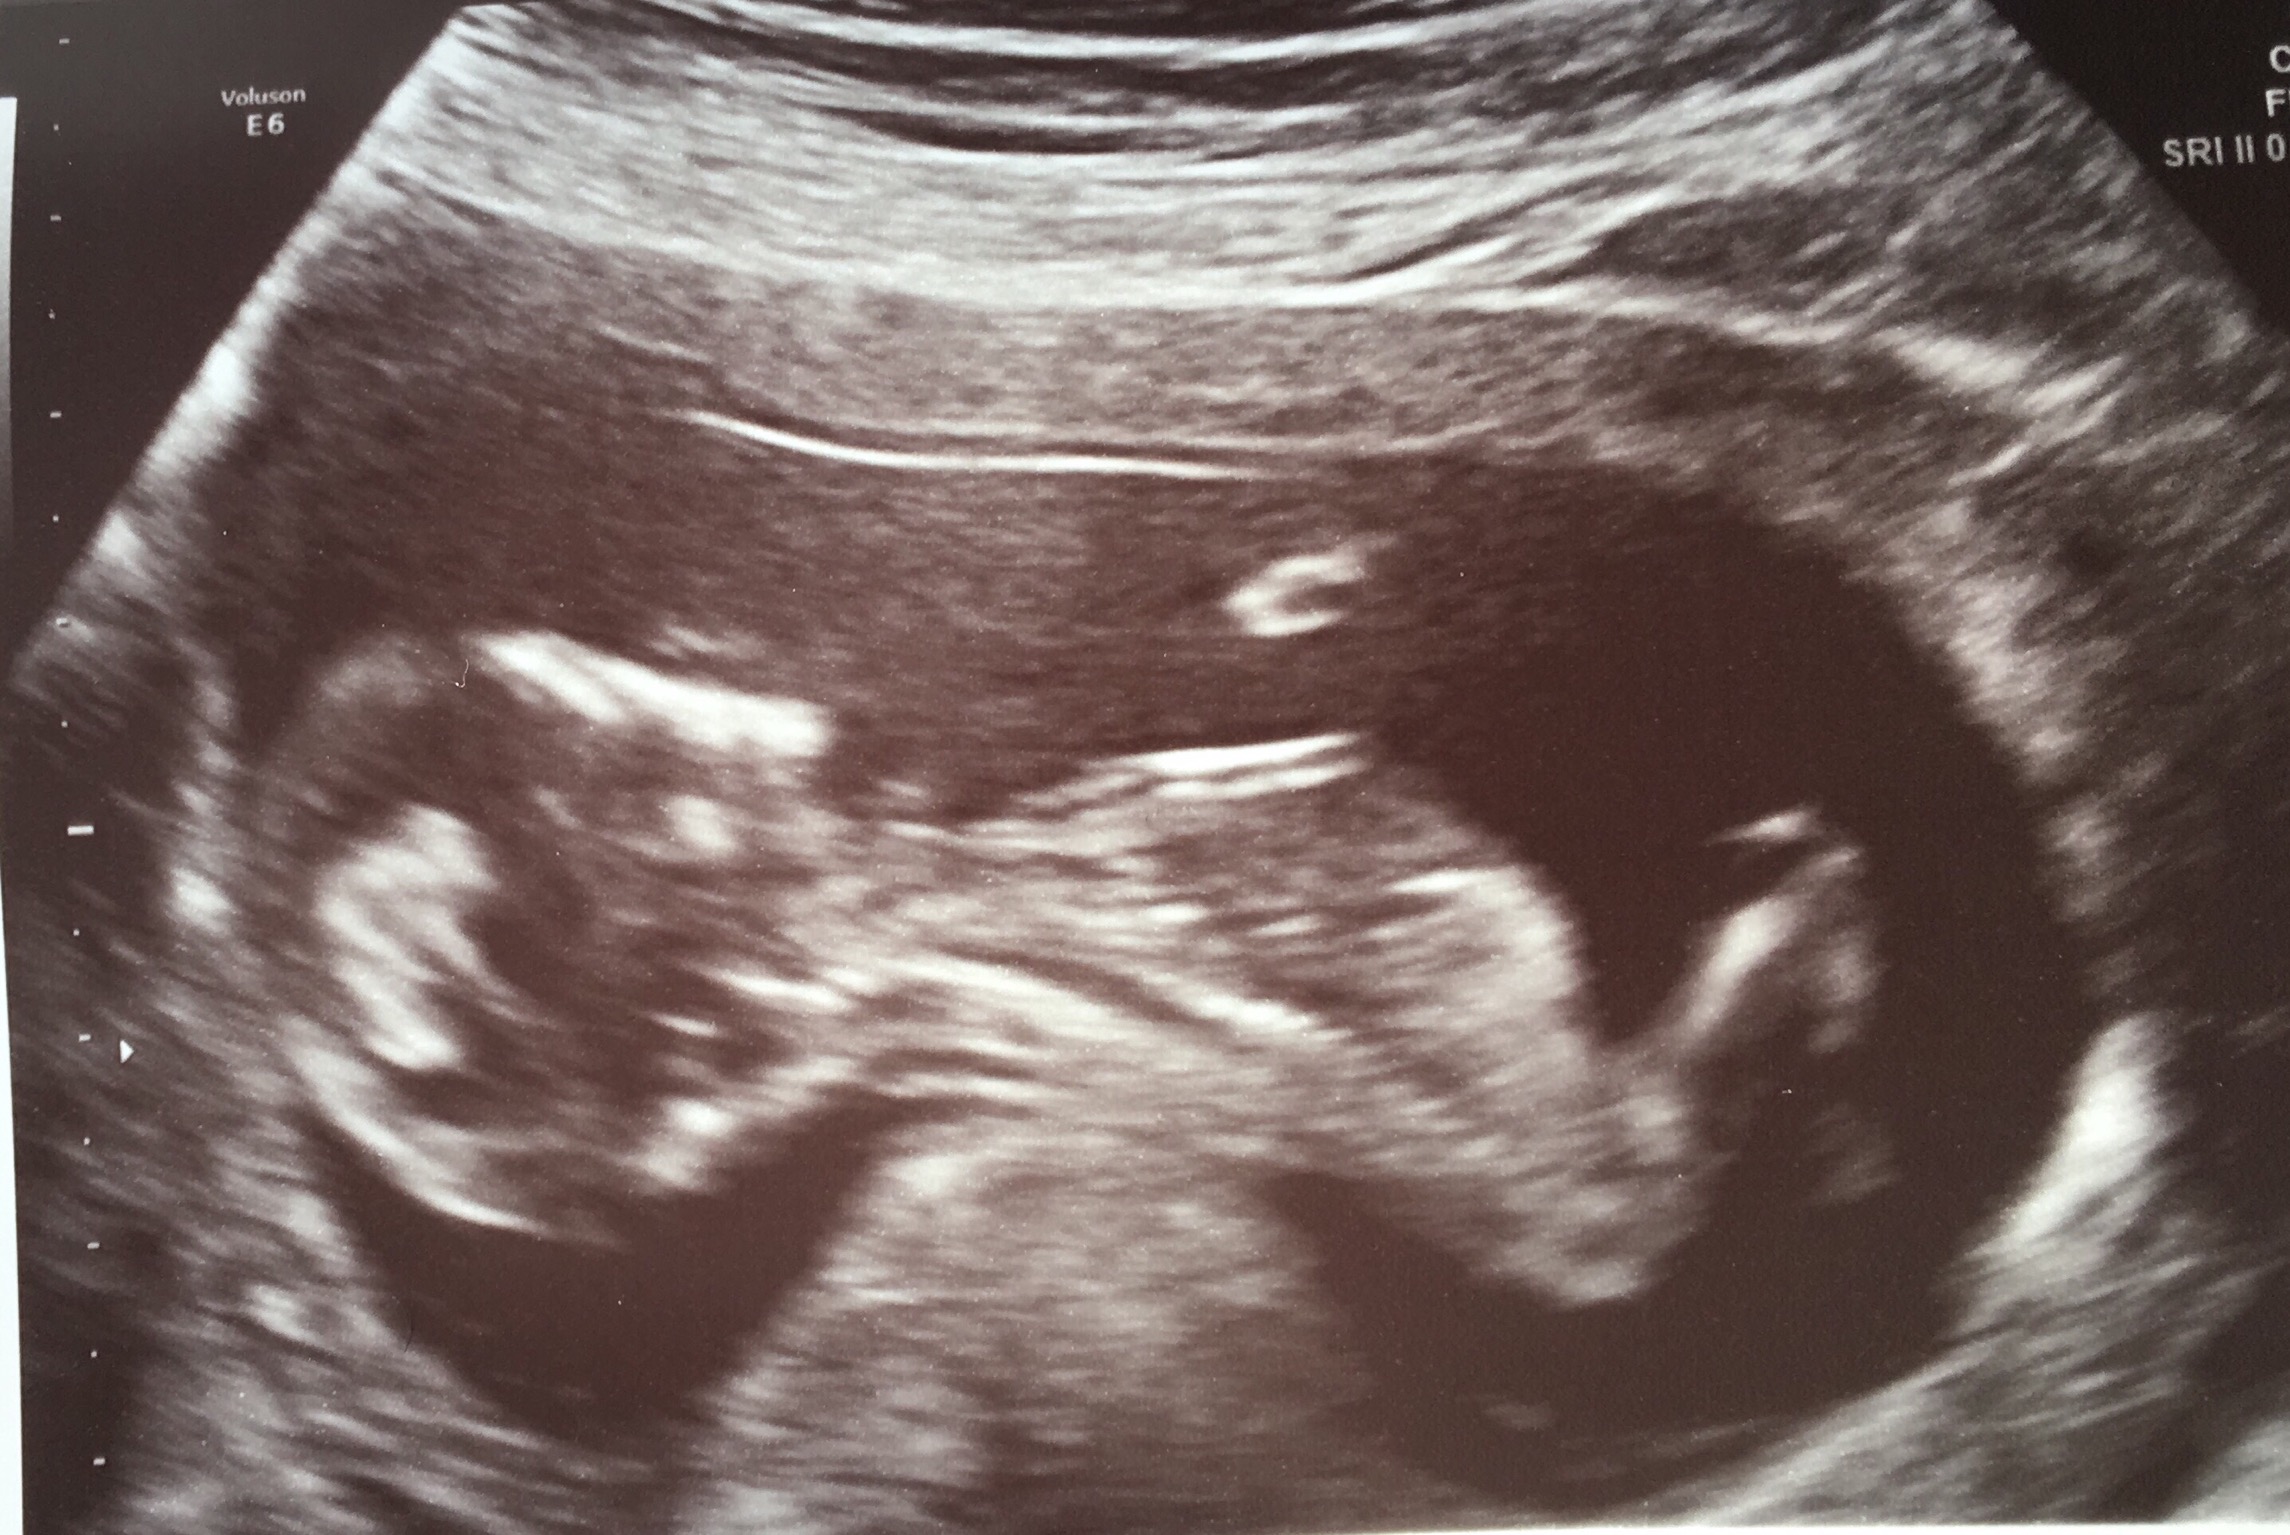

I’ve had both 12 week and 20 week scans and thought I wanted the surprise 3 rd time round but that’s proving more difficult as I approach my 4d scan in Feb. I already have 2 DS and would dearly love a little pink one to complete me but this baby is the last so either way I’m done as financially, spacially and practically we can’t afford anymore.I have thought girl from day one of conception for numerous reasons, timed conception (5-8dpo), feeling very nauseous, strong metallic taste in my mouth which is still present, bad breakouts all of which I didnt have with my boys. I’d be very interested to know what you all think 🤔 Attachment 38554Attachment 38556